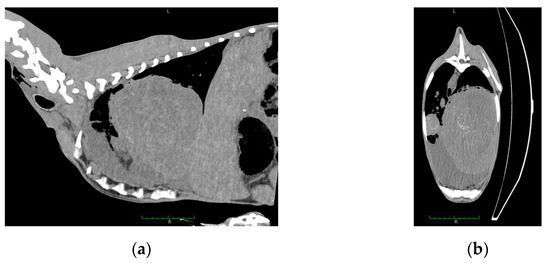

- Szalus-Jordanow, O.; Bonecka, J.; Pankowski, F.; Barszcz, K.; Tarka, S.; Kwiatkowska, M.; Polguj, M.; Mickiewicz, M.; Moroz, A.; Czopowicz, M.; et al. Postmortem imaging in goats using computed tomography with air as a negative contrast agent. PLoS ONE 2019, 14, e0215758. [Google Scholar] [CrossRef]